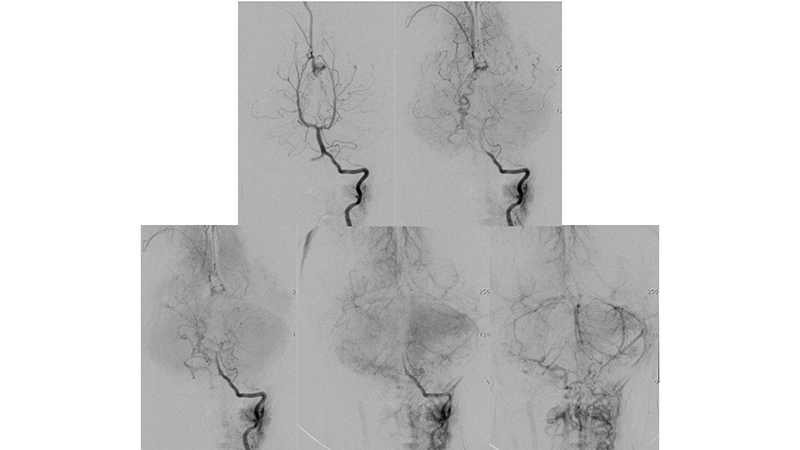

- Προσθιοπίσθια λήψη κατά την έγχυση στην δεξιά έσω καρωτίδα. Η αρτηριοφλεβώδης επικοινωνία της φλέβας του Γαληνού σκιαγραφείται από παλινδρόμηση στην δεξιά υποκλείδιο και σπονδυλική αρτηρία. Η φλεβική παροχέτευση του δεξιού εγκεφαλικού ημισφαιρίου γίνεται πολύ καθυστερημένα, λόγω απόφραξης των εγκαρσίων κόλπων αμφοτερόπλευρα (μαύρα βέλη).

- Πλαγία λήψη κατά την έγχυση στην δεξιά έσω καρωτίδα. Υπάρχει εξεσημασμένη φλεβική συμφόρηση του άνω οβελιαίου κόλπου, προς το σύστημα της φλέβας του Troland (μπλέ βέλος), τον σηραγγώδη κόλπο και τό έδαφος του προσθίου κρανιακού βόθρου (μαύρα βέλη) και το πτερυγοειδές πλέγμα.

- Προσθιοπίσθια λήψη κατά την έγχυση στην αριστερή έσω καρωτίδα. Η αρτηριοφλεβώδης επικοινωνία της φλέβας του Γαληνού σκιαγραφείται από την οπίσθια αναστομωτική αρτηρία. Η φλεβική παροχέτευση του αριστερού εγκεφαλικού ημισφαιρίου γίνεται πολύ καθυστερημένα, λόγω απόφραξης των εγκαρσίων κόλπων αμφοτερόπλευρα (μαύρα βέλη).

- Πλαγία λήψη κατά την έγχυση στην αριστερή έσω καρωτίδα. Η φλεβική παροχέτευση της αρτηριοφλεβώδους επικοινωνίας προς το σύστημα του άνω οβελιαίου κόλπου (κόκκινα βέλη) με εξεσημασμένη φλεβική συμφόρηση και κινητοποίηση παράπλευρων διαμυελικών φλεβών προς το σύστημα της επιπολής μέσης εγκεφαλικής φλεβός (μπλέ βέλος) και διά του σφηνοβρεγματικού κόλπου προς τον σηραγγώδη κόλπο ενώ το εν τω βάθει φλεβικό δίκτυο αποχετεύεται μέσω των αναστομώσεων με το σύστημα της εν τω βάθει μέσης εγκεφαλικής φλεβός (διακεκομμένο μπλέ βέλος) προς το σύστημα επίσης του σηραγγώδους κόλπου.